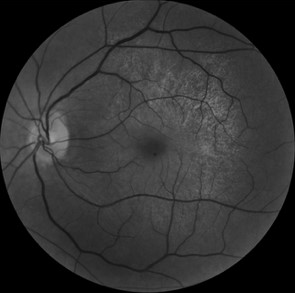

We report the case of a 45-year-old woman presented with complaints of decreased vision in the left eye (LE). Her best-corrected visual acuity in the RE was 10/10 and left eye was 06/10. Both eyes (BEs) anterior segment examination was unremarkable. There was no history of night blindness or decreased vision in any of the family members. Fundus examination revealed presence of retinal pigment epithelial (RPE) hypopigmentation and atrophy at the posterior pole along with an enhanced golden tapetal sheen seen in posterior pole of the left eye (figure 1A). Fundus autofluorescence revealed a crescent-shaped hyperautofluorescence in LE (figure 1B). Spectral domain optical coherence tomography (SD-OCT) revealed a normal foveal contour in the left eye with thining of photoreceptor layer to the macula in LE with small drusens(figure 2). Based on the multimodal imaging findings, we suspected a starting manifestations of retinitis pigmentosa and the patient was advised for genetic analysis revealing mutation on x-linked RPGR/RP3 GENE then set for observation and a routine follow-up.

A B

Figure1: A: fundus photo showing tapetal like reflex in left eye B: fundus autofluorescence showing hyperreflectivity of the posterior pole by atrophy starting of the retinal pigmented epithelium